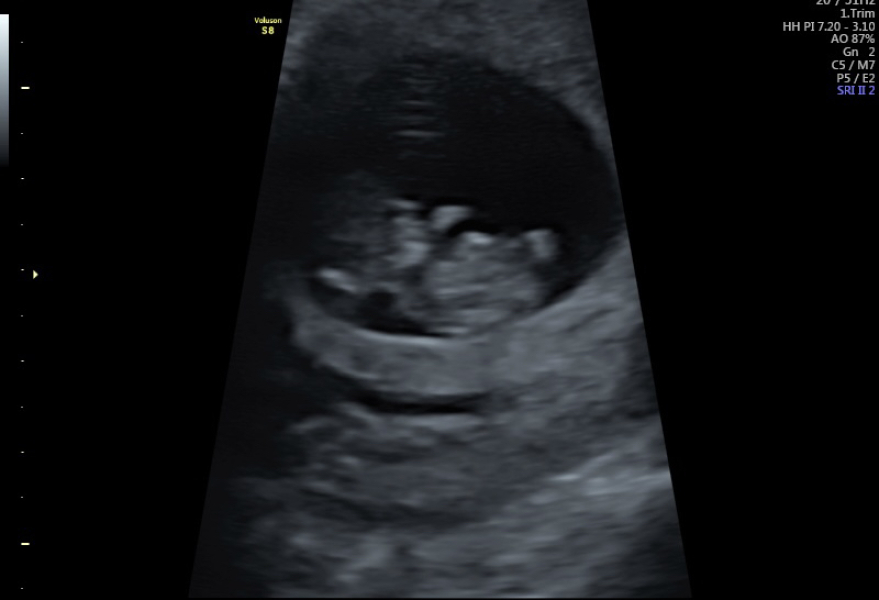

MadsAngel · 25/02/2024 11:57

All is well and saw our wiggly little baby waving arms and legs around🥰 Measuring as it should be at 10 weeks